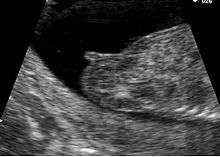

Genital tubercle of female at fourteen weeks